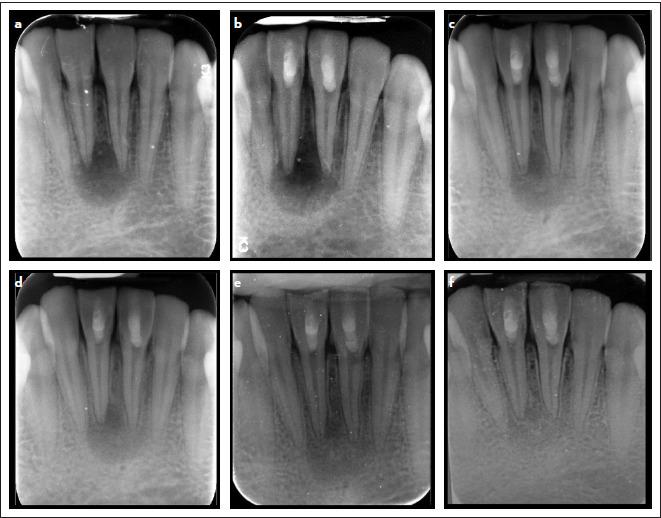

The study involved 36 patients with mature teeth with necrotic pulp and apical periodontitis. The patient underwent a regenerative treatment that utilized the blood clot technique. Teeth were randomly allocated to either the intervention, Biodentine, group (n=18) or the control, MTA, group (n=18). The healing of periapical lesions and tooth sensibility were evaluated throughout follow-up visits for up to 18 months.

The study analyzed 31 patients; two patients within the biodentine group and three in the MTA group were lost to follow-up. After 18 months, both groups showed effective healing of periradicular lesions; 21 out of 31 patients (67.7%) were healed, ten patients (32.3%) were healing, and no failure cases occurred. There were no significant differences between the groups (p=1.00). More than 70% (22 out of 31 patients) regained their sensibility in their teeth, and the groups had no statistically significant difference (p=0.703).

Regenerative treatment using blood clots with either MTA or Biodentine effectively resolved periapical lesions and regained the sensibility of mature teeth.